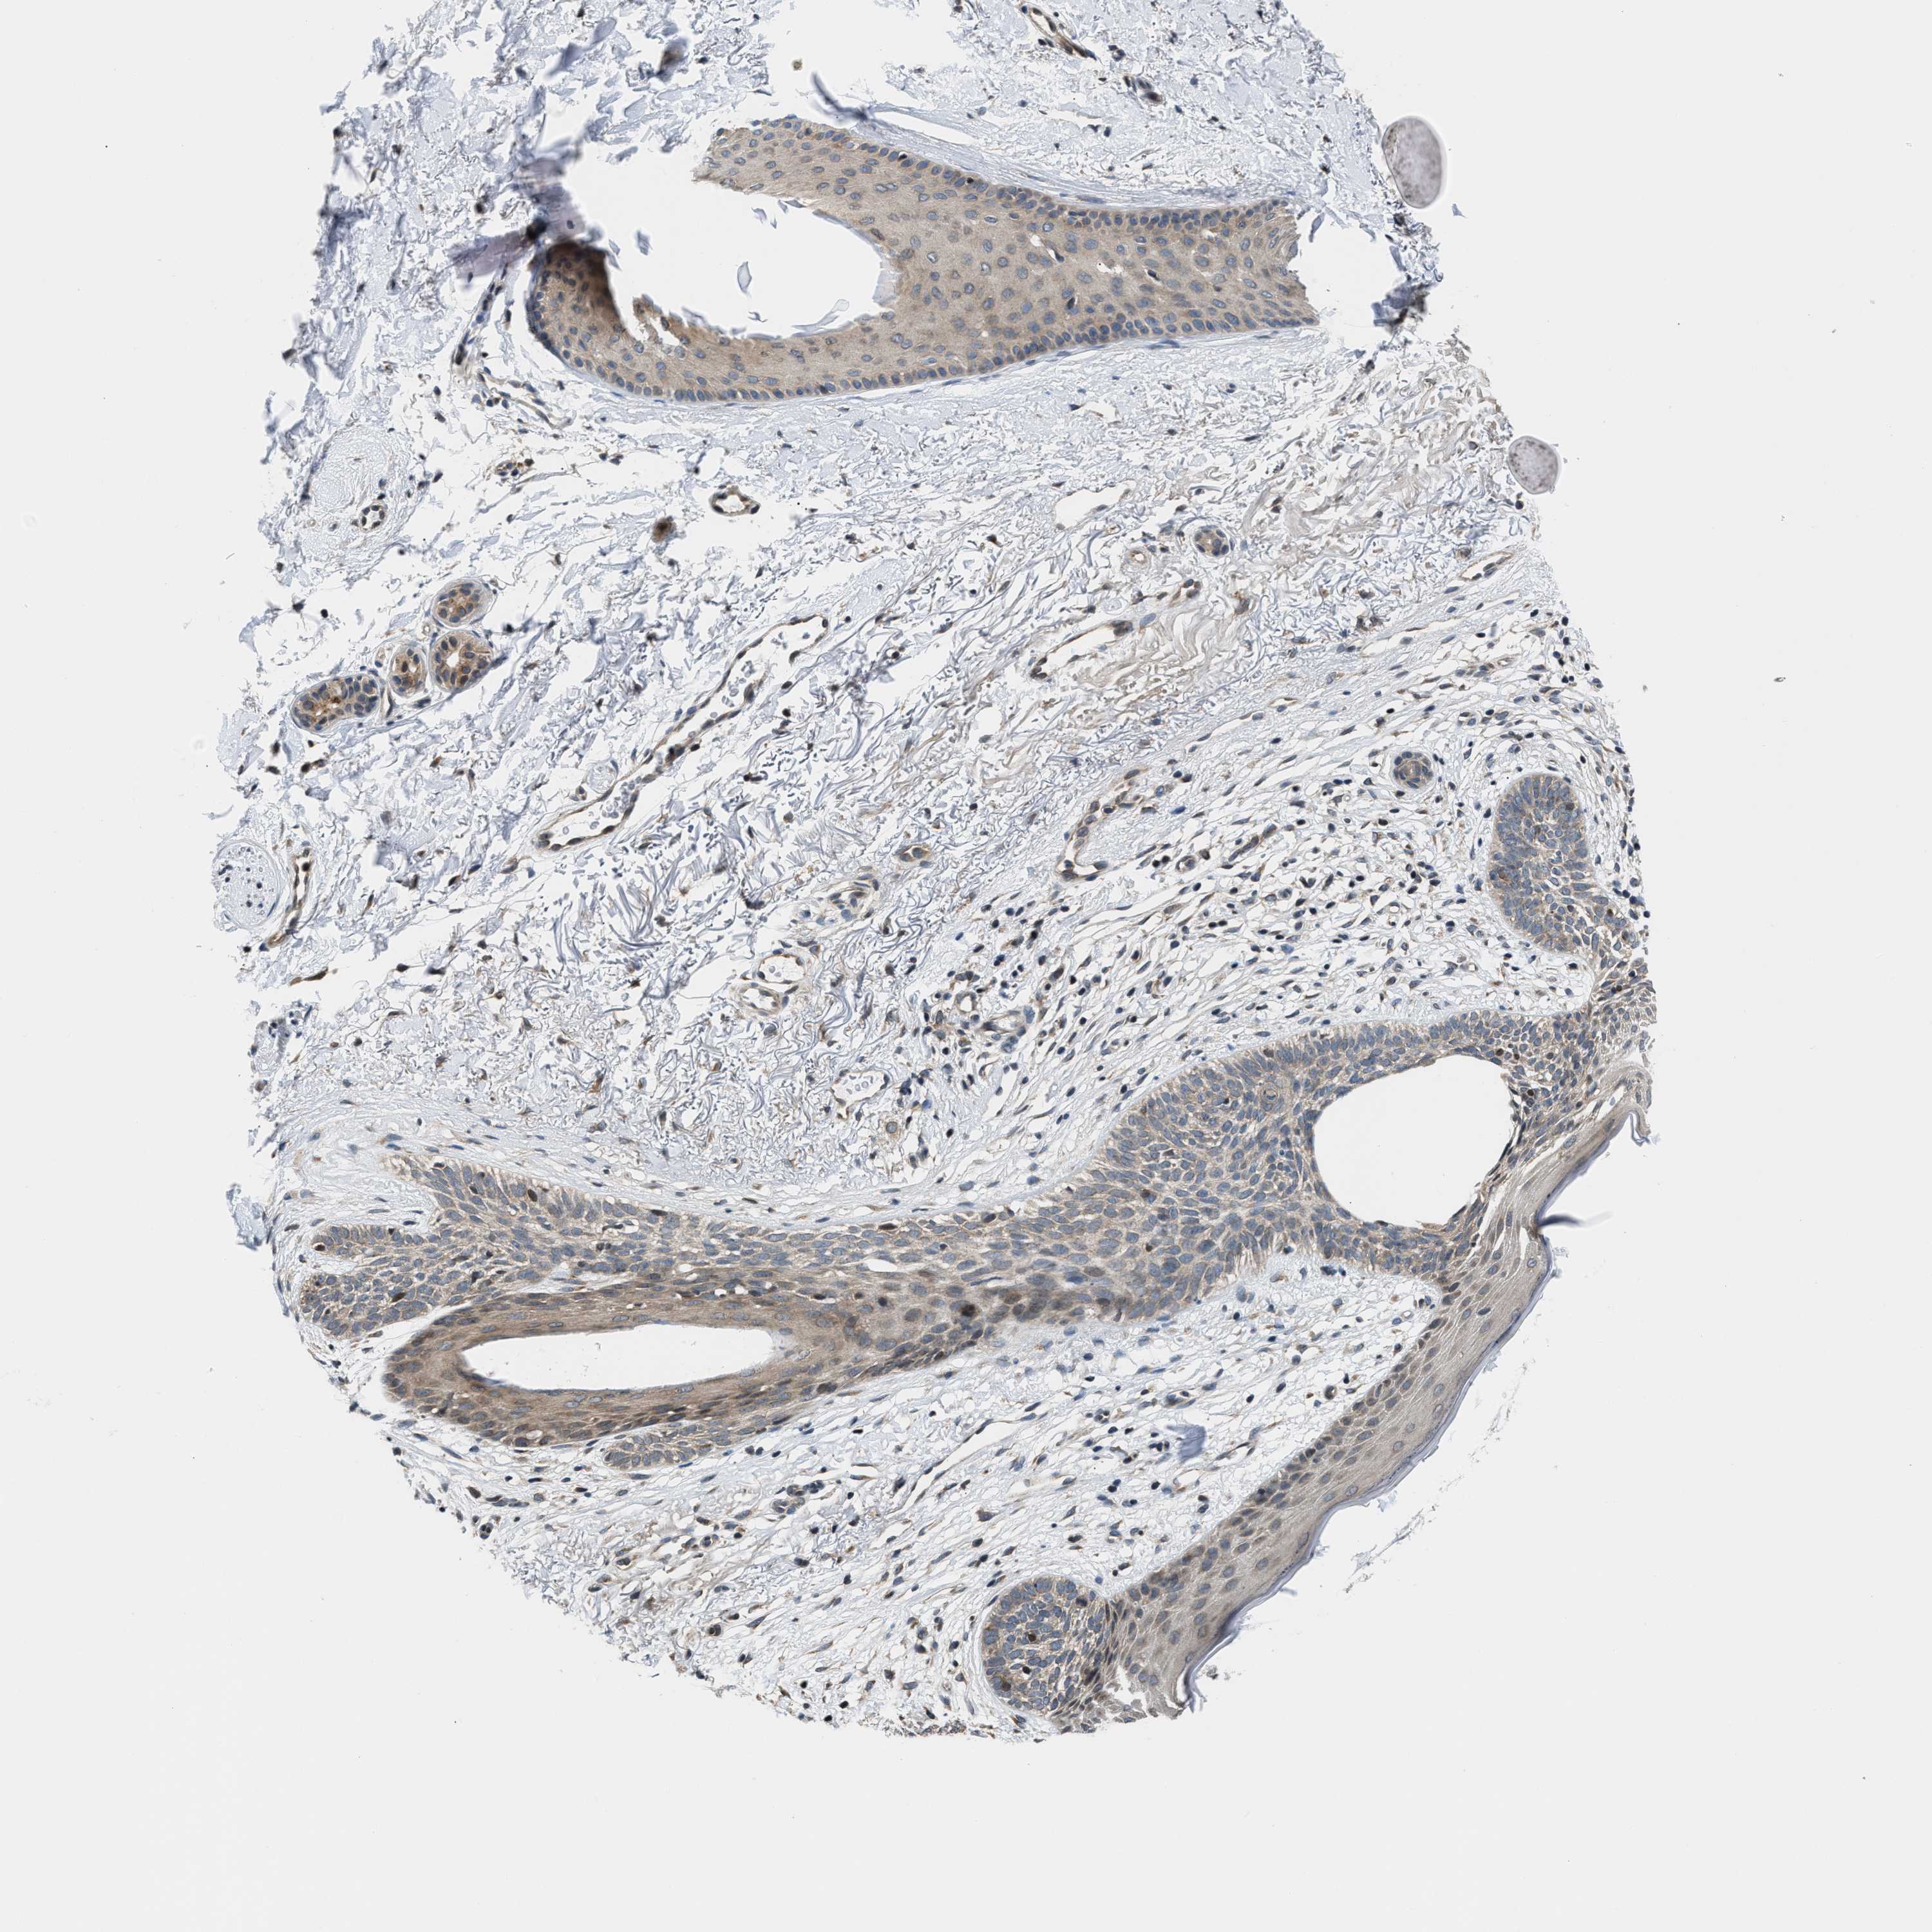

SKIN CANCER - Protein expressioni

A mouse-over function shows sample information and annotation data. Click on an image to view it in a full screen mode. Samples can be filtered based on level of antibody staining by selecting one or several of the following categories: high, medium, low and not detected. The assay and annotation is described here.

Antibody stainingi

Antibody staining in the annotated cell types in the current human tissue is reported as not detected, low, medium, or high, based on conventional immunohistochemistry profiling in selected tissues. This score is based on the combination of the staining intensity and fraction of stained cells.

Each image is clickable and will lead to virtual microscopy that enables deeper exploration of all samples and also displays staining intensity scores, fraction scores and subcellular localization as well as patient and tissue information for each sample.

Antibody HPA026303

Antibody CAB020822

Squamous cell carcinoma, NOS

Squamous cell carcinoma, metastatic, NOS